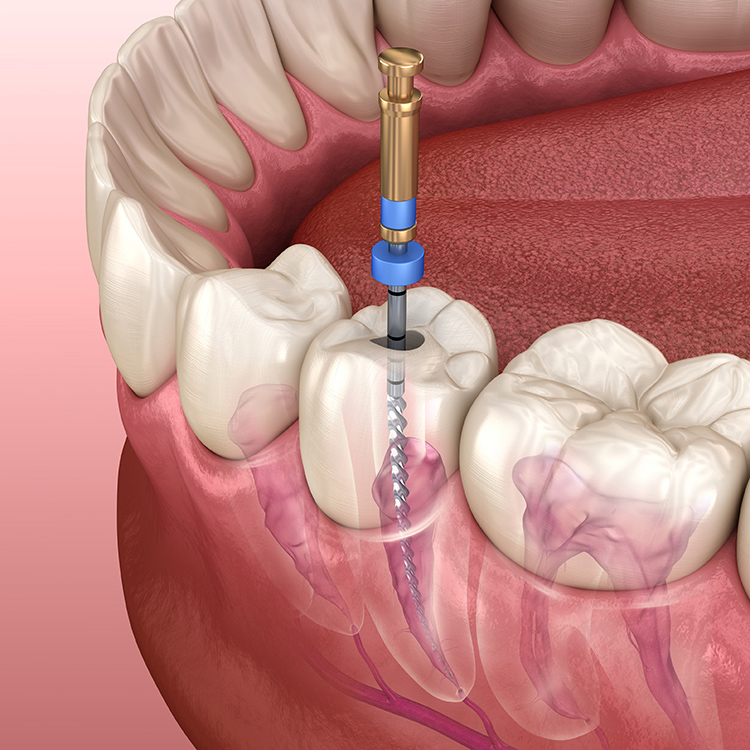

사실 신경치료는 감염된 신경을 아예 제거해서 없애는 치료이고,

충치신경치료를 위해서는 불편하시겠지만

일주일 간격으로 약 4~5회 정도 치과에 오셔서 치료를 꾸준히 받으셔야 하는데요.

신경치료를 하다가 중단하거나, 치료 사이사이 기간이 길어지게 되면 오히려 더 위험합니다.

물론 임시약제로 막아드리긴 하지만 신경치료를 위해 치아에 구멍도 뚫려있고,

치아 내부가 텅 빈 상태에서 씹는 힘과 같은 자극이 가게 되면

약해져있는 치아에 금이 가거나 부러질 가능성이 더 높기 때문입니다.